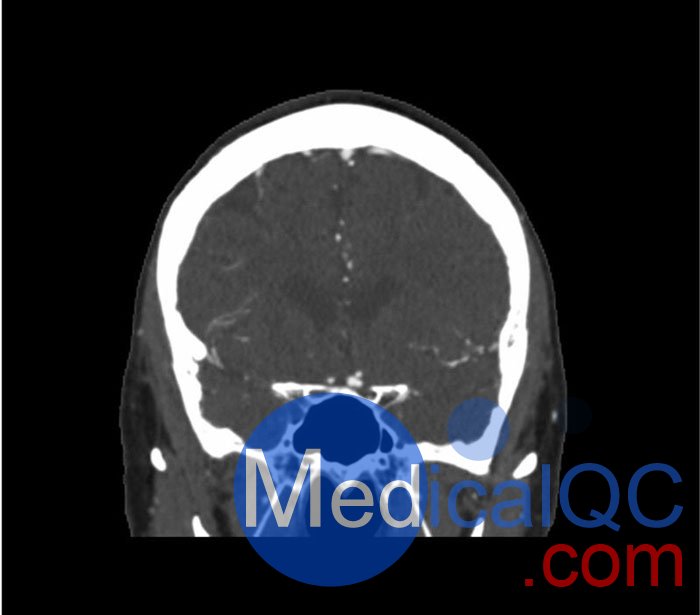

WEK50-03動脈瘤頭模,WEK50-03血管造影CTA頭模是頭部 CTA 動脈瘤模型

模擬造影劑動脈期頭部增強(qiáng)(CT血管造影)。 它覆蓋了頂點(diǎn)枕骨大孔。

模型有三個顱內(nèi)動脈瘤

大腦中動脈 (MCA) 的前部

交通動脈 (ACoA) 和基底動脈動脈。

該體??捎糜贑T(包括CBCT)評估和優(yōu)化成像性能和人工智能診斷。 這是也適合培訓(xùn)目的。

WEK50-03動脈瘤頭模,WEK50-03血管造影CTA頭模影像圖:

更多效果和DICOM數(shù)據(jù)請聯(lián)系我們

SAG: